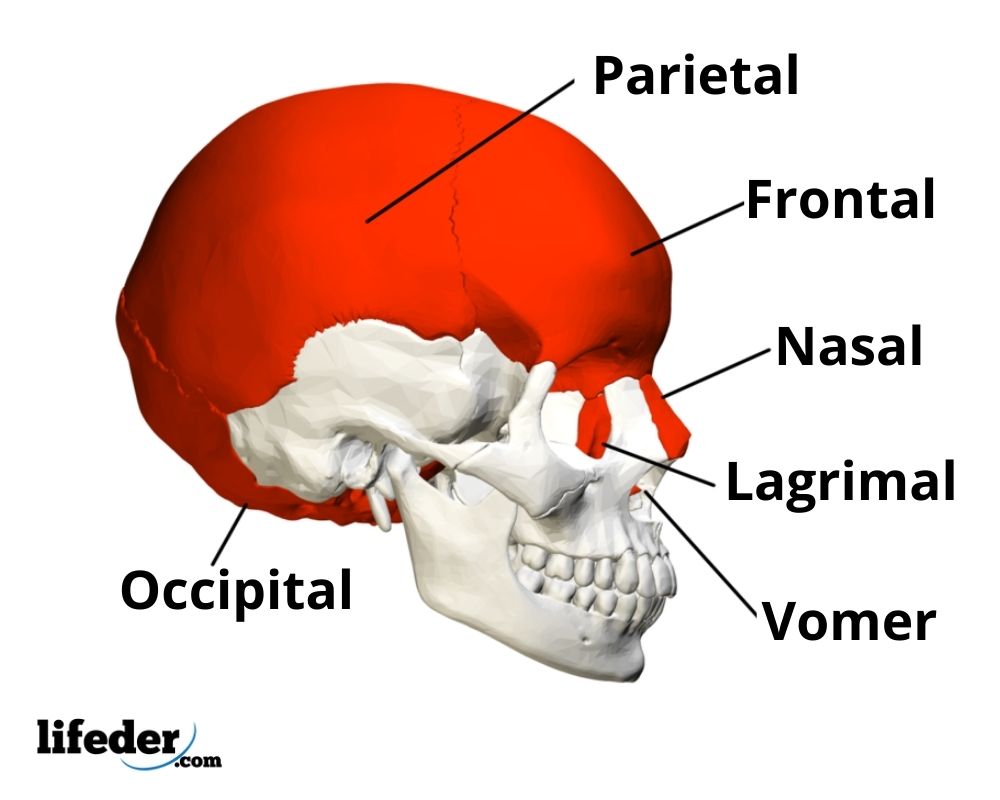

El cráneo, también llamado bóveda craneal, está compuesto por una serie de huesos, que incluyen el frontal, el parietal, el occipital, el nasal, el temporal, el lacrimal y los esfenoides.

El rol principal del cráneo es proteger al cerebro de los daños que se podrían generar por golpes o caídas. Los huesos del cráneo también son los responsables de formar las cuencas de los ojos y las fosas nasales.

1- El hueso frontal

Como su nombre indica, este hueso ocupa toda la parte frontal del cráneo.

2- El hueso parietal

Los huesos parietales son dos y se encuentran uno a cada lado de la cabeza, entre el hueso occipital y el hueso frontal.

3- El hueso occipital

El hueso occipital está ubicado en la parte posterior del cráneo. En este se encuentra el agujero occipital, el cual es una apertura que conecta al cráneo con la columna vertebral.

4- El hueso temporal

Este hueso ocupa la parte inferior y lateral del cráneo.

5- Los huesos esfenoides

Los esfenoides se encuentran en la parte inferior del cráneo, en la base, y presentan una cavidad en la que se ubica la hipófisis.